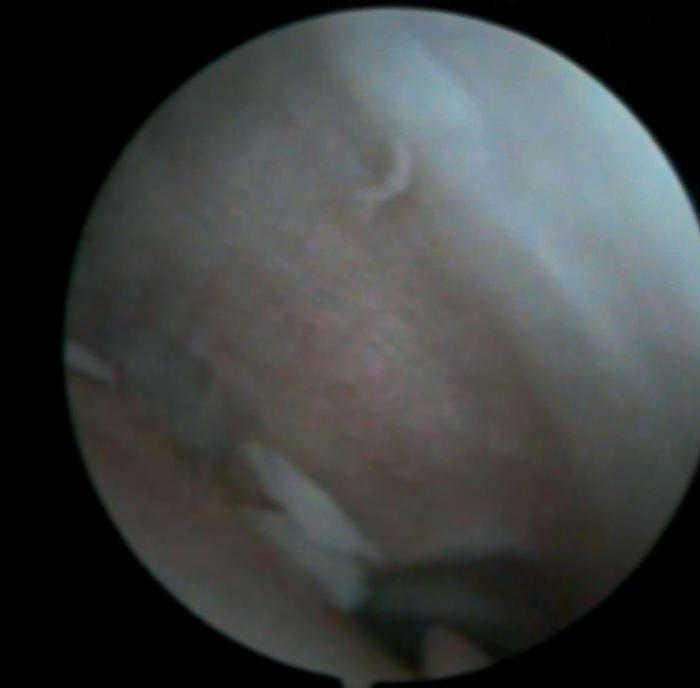

Figura 4 Artroscopia. Lesión condral amplia en rótula, faceta externa y cresta condral.

Se practica artroscopia, en la que se observan (figs. 2, 4, 6-8):

• Lesión condral anfractuosa extensa, con fragmentos inestables en cresta de la rótula y en faceta externa, de grado III.